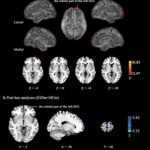

Researchers using functional MRI (fMRI) have found differences in the brains of men and women who are addicted to online gaming, according to...